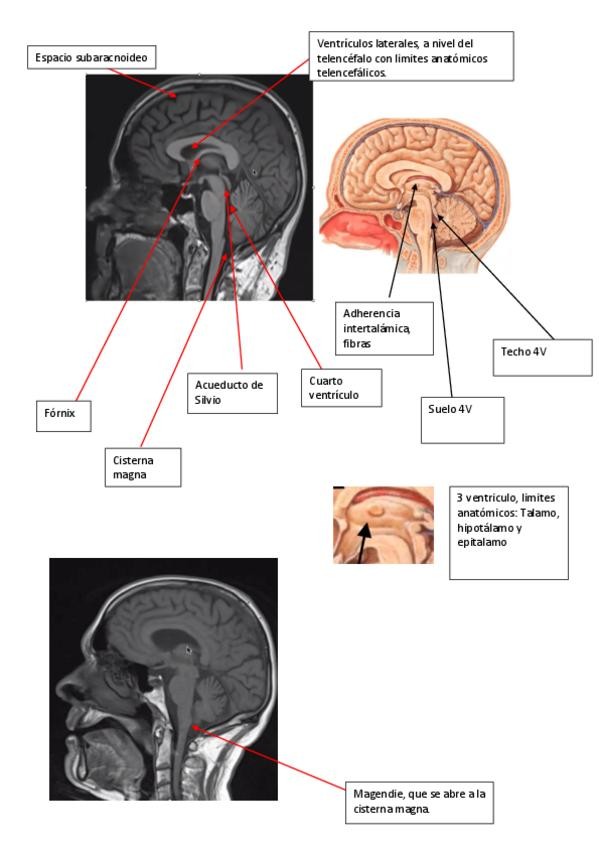

cortes imágenes prácticas examen